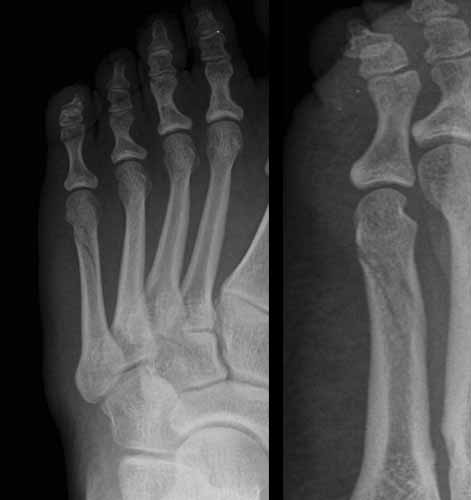

A la imatge: Imatges radiològiques d’una fractura no desplaçada del cinquè metatarsià. En aquest tipus de fractures n’hi haurà prou amb la immobilització amb un guix o una bota ortopèdica per a la seva curació.